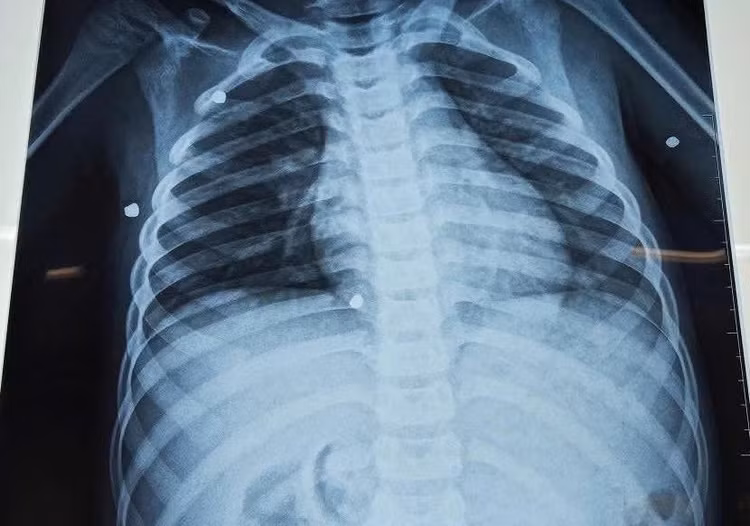

Kết quả chụp X-quang cho thấy có nhiều dị vật cản quang nằm rải rác ở nhiều vị trí trong cơ thể. Ảnh: Trần Tuyền

Qua thăm khám, các bác sĩ phát hiện nhiều vết thương do hỏa khí tại vùng ngực và hai tay. Kết quả chụp X-quang cho thấy có nhiều dị vật cản quang nằm rải rác ở nhiều vị trí trong cơ thể.